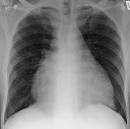

Breitbasig aufsitzendes nach links verbreitertes Herz, normal gewoelbte Zwerchfelle. German term or phrase: breitbasig aufsitzendes Herz Lungenzeichnung. BMW Mobiler Service: Die kostenlose Pannenhilfe von BMW. Beta Alanin ist nicht gefährlich es hilft eher sehr gut wenn man. Crataegus laevigatus Paul Scarlet - Rotdorn Rotdorn, Crataegus laevigatus Paul Scarlet, und Weißdorn, Crataegus monogyna, kann man sehr gut schneiden und sogar heckenartig ziehen.

Breitbasig aufsitzendes Herz Lungenzeichnung broad